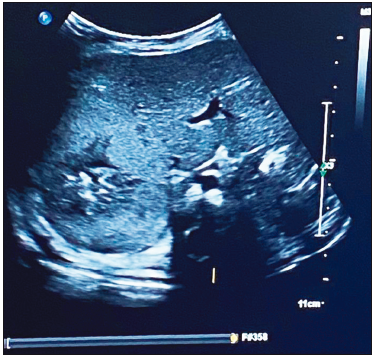

Al ingreso presentó hipotonía axial sin dismorfias. Se solicitó una ecografía abdominal en la que se visualizó una imagen ecogénica hepática (segmento VI - VII), con bordes difusos, de 4 x 3.5 x 3.1 cm, que coincidió bioquímicamente con el aumento de las enzimas hepáticas y leve anemia. La AFP estaba dentro de valores normales para la edad (42,334 ng/ml), con plaquetas normales. (Figuras 1 A B C).

Figura 1. B